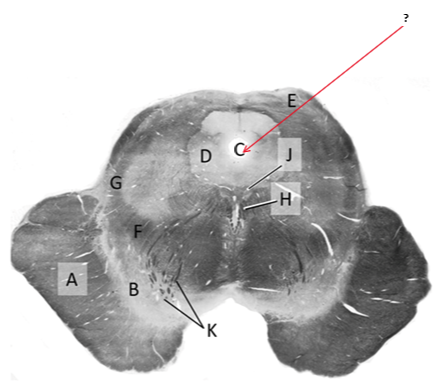

Name this and state its function.

Tectum.

Name this and its divisions+ function?

Substantia nigra.

Cerebral aqueduct.

Crus cerebri.

Medial Lemniscus.

Name this, what is it and state its function.

Lateral lemniscus.

Name this, state its function[2 marks] and how it goes about its function[4 marks].

Medial longitudinal lemniscus.

How?

Oculomotor nucleus.

Name this, state its function[3 marks] and cells involved contributing to function.

Periaqueductal grey.

Root fibres of Oculomotor nerves(CN III).